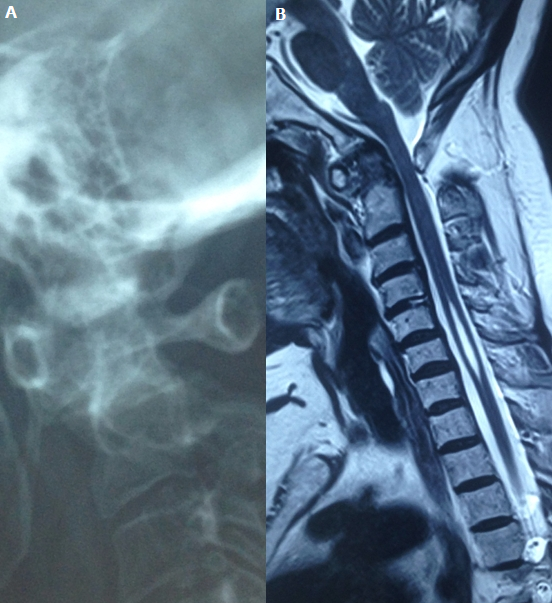

We report a case of 64-year-old Tunisian woman with a 12-year history of rheumatoid arthritis, who presented with a 3-month history of increasing inflammatory neck pain. Neurological examination noted a quadripyramidal syndrome without any neurological deficit. Radiographs of her neck showed ananterior atlantoaxial subluxation (A). MRI revealed a pannus around the atlanto axial joint. It also showed a co-existing syringomyelia (B). The cervical spine is frequently involved in patients with rheumatoid arthritis. However, rheumatoid atlantoaxial subluxation with syringomyelia is very rare. Many hypothesised mechanisms were suggested for the syrinx formation. The most commonly admitted, suggested that atlanto axial subluxation may reduce the rate of ascending cerebrospinal fluid, so it would travel through the spinal cord producing syringomyelia.